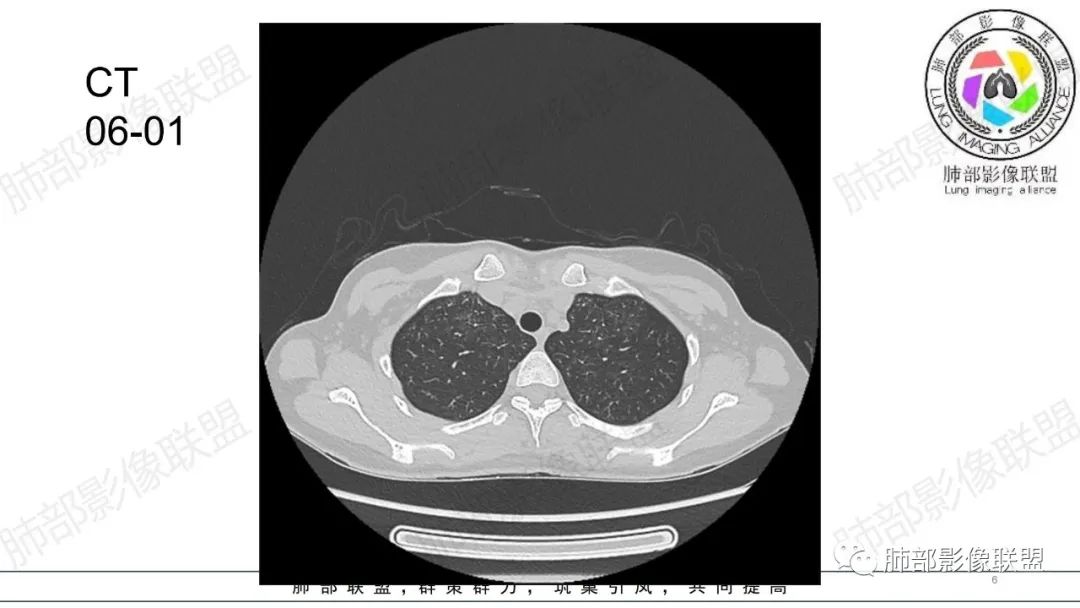

影像资料

34岁女性患者,“哮喘”病史30年,近期有可疑刺激性气体吸入史;因乏力半年,咳嗽、憋气、发热4天就诊;6.1CT提示双肺广泛毛玻璃影及粟粒样结节,胸膜下闲置及血管周闲置,可见树丫征,部分小叶间隔增厚。考虑:1.过敏性肺泡炎,有可疑刺激气体接触史,胸膜下闲置,广泛毛玻璃影,地图样分布,粟粒结节边界模糊,支持过敏性肺泡炎,但糖皮激素治疗效果不佳,且动态复查血常规血红蛋白进行性降低,过敏性肺泡炎 不符合;2.肺含铁血黄素沉积症:患者30“哮喘”病史,可能为肺含铁症状,肺部CT提示双肺弥漫毛玻璃影及粟粒结节影,中下肺明显,肺底部分小叶间隔增厚,近期咳嗽、憋气、发热,血常规血红蛋白进行性下降,考虑肺含铁急性期症状,但临床无咯血症状,肺含铁不典型。综合考虑:肺含铁血黄素沉积症>过敏性肺泡炎。

年轻女性 ,急性喘息发热,肺部影像弥漫磨玻璃密度,部分细小腺泡结节,胸膜下黑线显示,短期复查,病变密度增高,下肺明显,血管周围肺组织累及较少、且逐渐成小叶间隔分布。考虑弥漫肺泡内病变,并经淋巴道转移,下肺比上肺明显,多为免疫细胞功能下肺较强。1.过敏性肺泡炎,有相关病史,三层密度特点、头尾测分布,符合。2 肺泡微石症,多有钙化,且缓慢起病,病程不太符合,放待排。3 吸入相关肺损伤,有病史,疾病演变过程也符合渗出-肉芽肿改变,建议详细询问病史。4 感染性病变,结核?病变气道分布为主,如此弥漫且没有树丫不符合。5.巨细胞病毒,可以磨玻璃 结节 改变,没有免疫缺陷病史。最后考虑吸入所致 1过敏性肺泡炎、吸入性肺损伤 鉴别肺泡微石症。